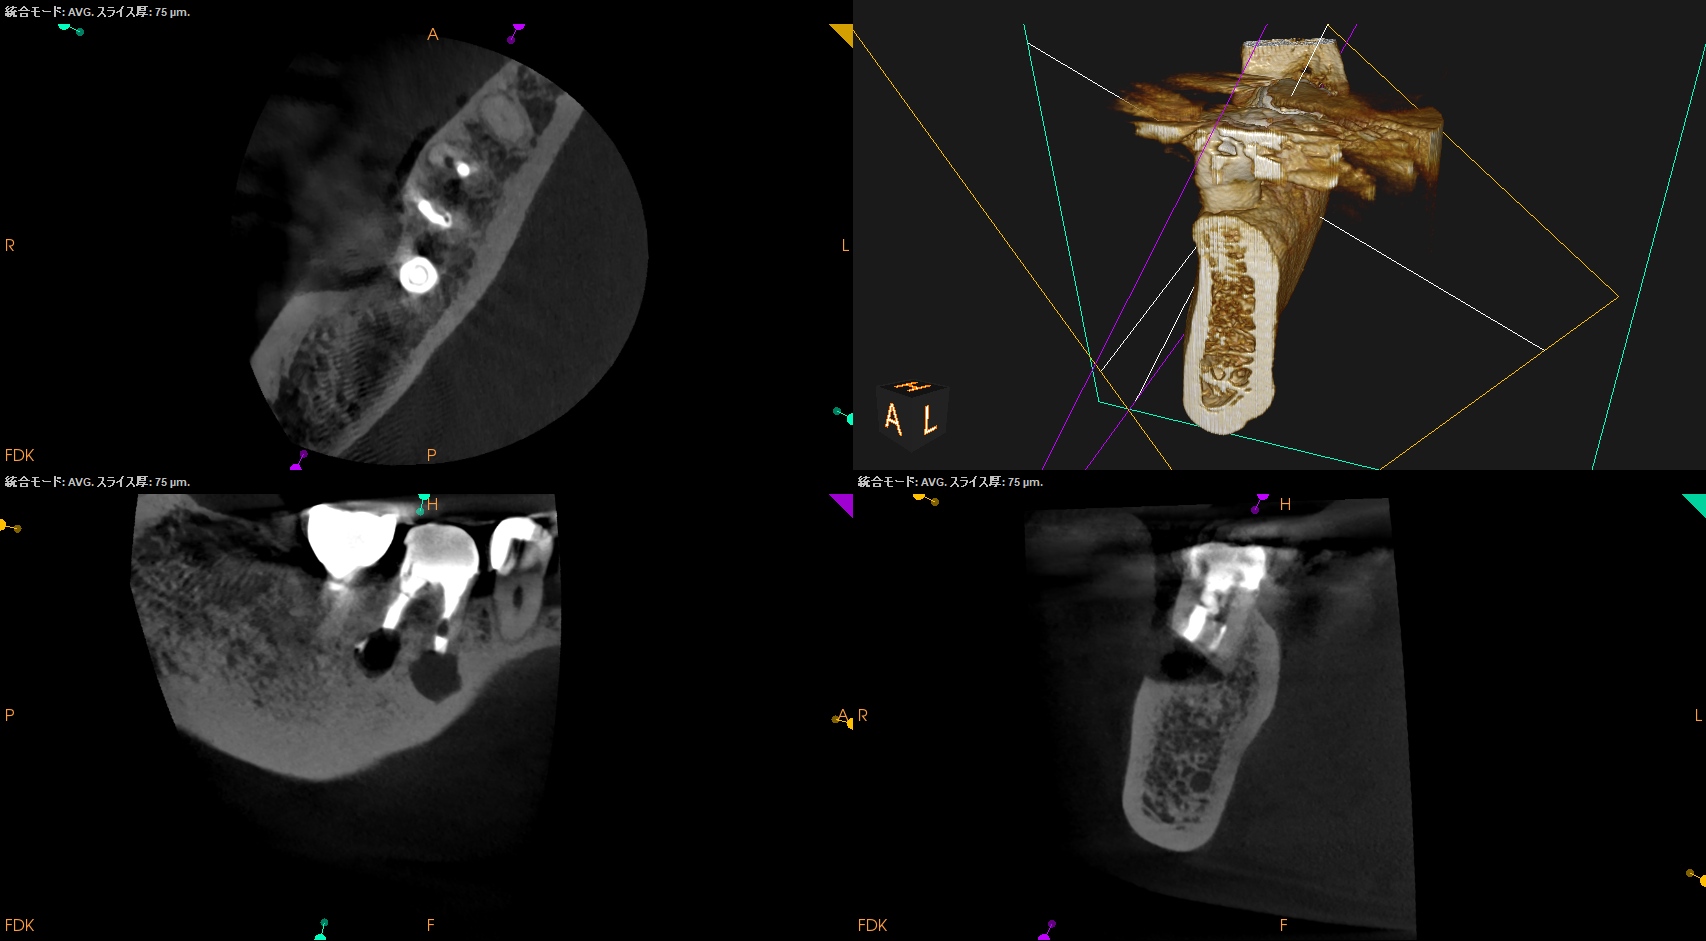

CBCT(2025.10.27)

MB

ML

DB

DL

MのApexに到達するにはCEJよりも12.5mm下方の歯槽骨を2mm削合(Osteotomy)しなければならない。

Apexを見つけたら3mm切断するがこの時の頬舌的な幅径が6.3mmだ。

リンデマンバーの半分よりも長い。

またDはApexに到達するには、CEJよりも13mm下方の歯槽骨を3mm削合する必要がある。

まさに…芋掘りだ。。。